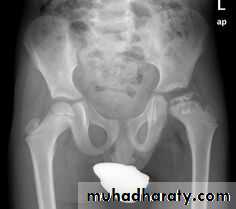

DEVELOPMENTAL DYSFLASIA OF HIP (CONGENITAL DISLOCATION OF THE HIP)

• An abnormally lax joint capsule allows the femoral head to fall out of the acetabulum, leading to deformation.• Predisposing factors for the development of CDH are:

• * Abnormal ligamentous laxity (effect of estrogen; fema1e:male = 6:l)

• * Acetabular dysplasia .

• CDH occurs most commonly (70%) in the left hip. Bilateral involvement is seen in 5%.

• Radiographic features

• US (commonly used today) at 1-3 months

• * Normal femoral head is covered at least 50% by acetabulum , In CDH < 50% of femoral head is covered by acetabulum .

Plain film

At 3-6 months :By doing special veiw (Von Rosen veiw )by abduction of the thigh 45 degree and internal rotation .

In DDH the lines that drown through the femura will meet in higher level than the normally should at lumbosacral joint .

6 months and later

* AP veiw ( femural epiphysis are visualized ):* Superolateral displacement of proximal femur (disturbed shenton’s line )

* Increase in acetabular angle

* Small capital femoral epiphysis

Femoral head is located lateral to Perkin's line

* Other features that are sometimes present

Abnormal sclerosis of the acetabulum

Shallow acetabulum

Formation of a false acetabulurn

Delayed ossification of femoral head